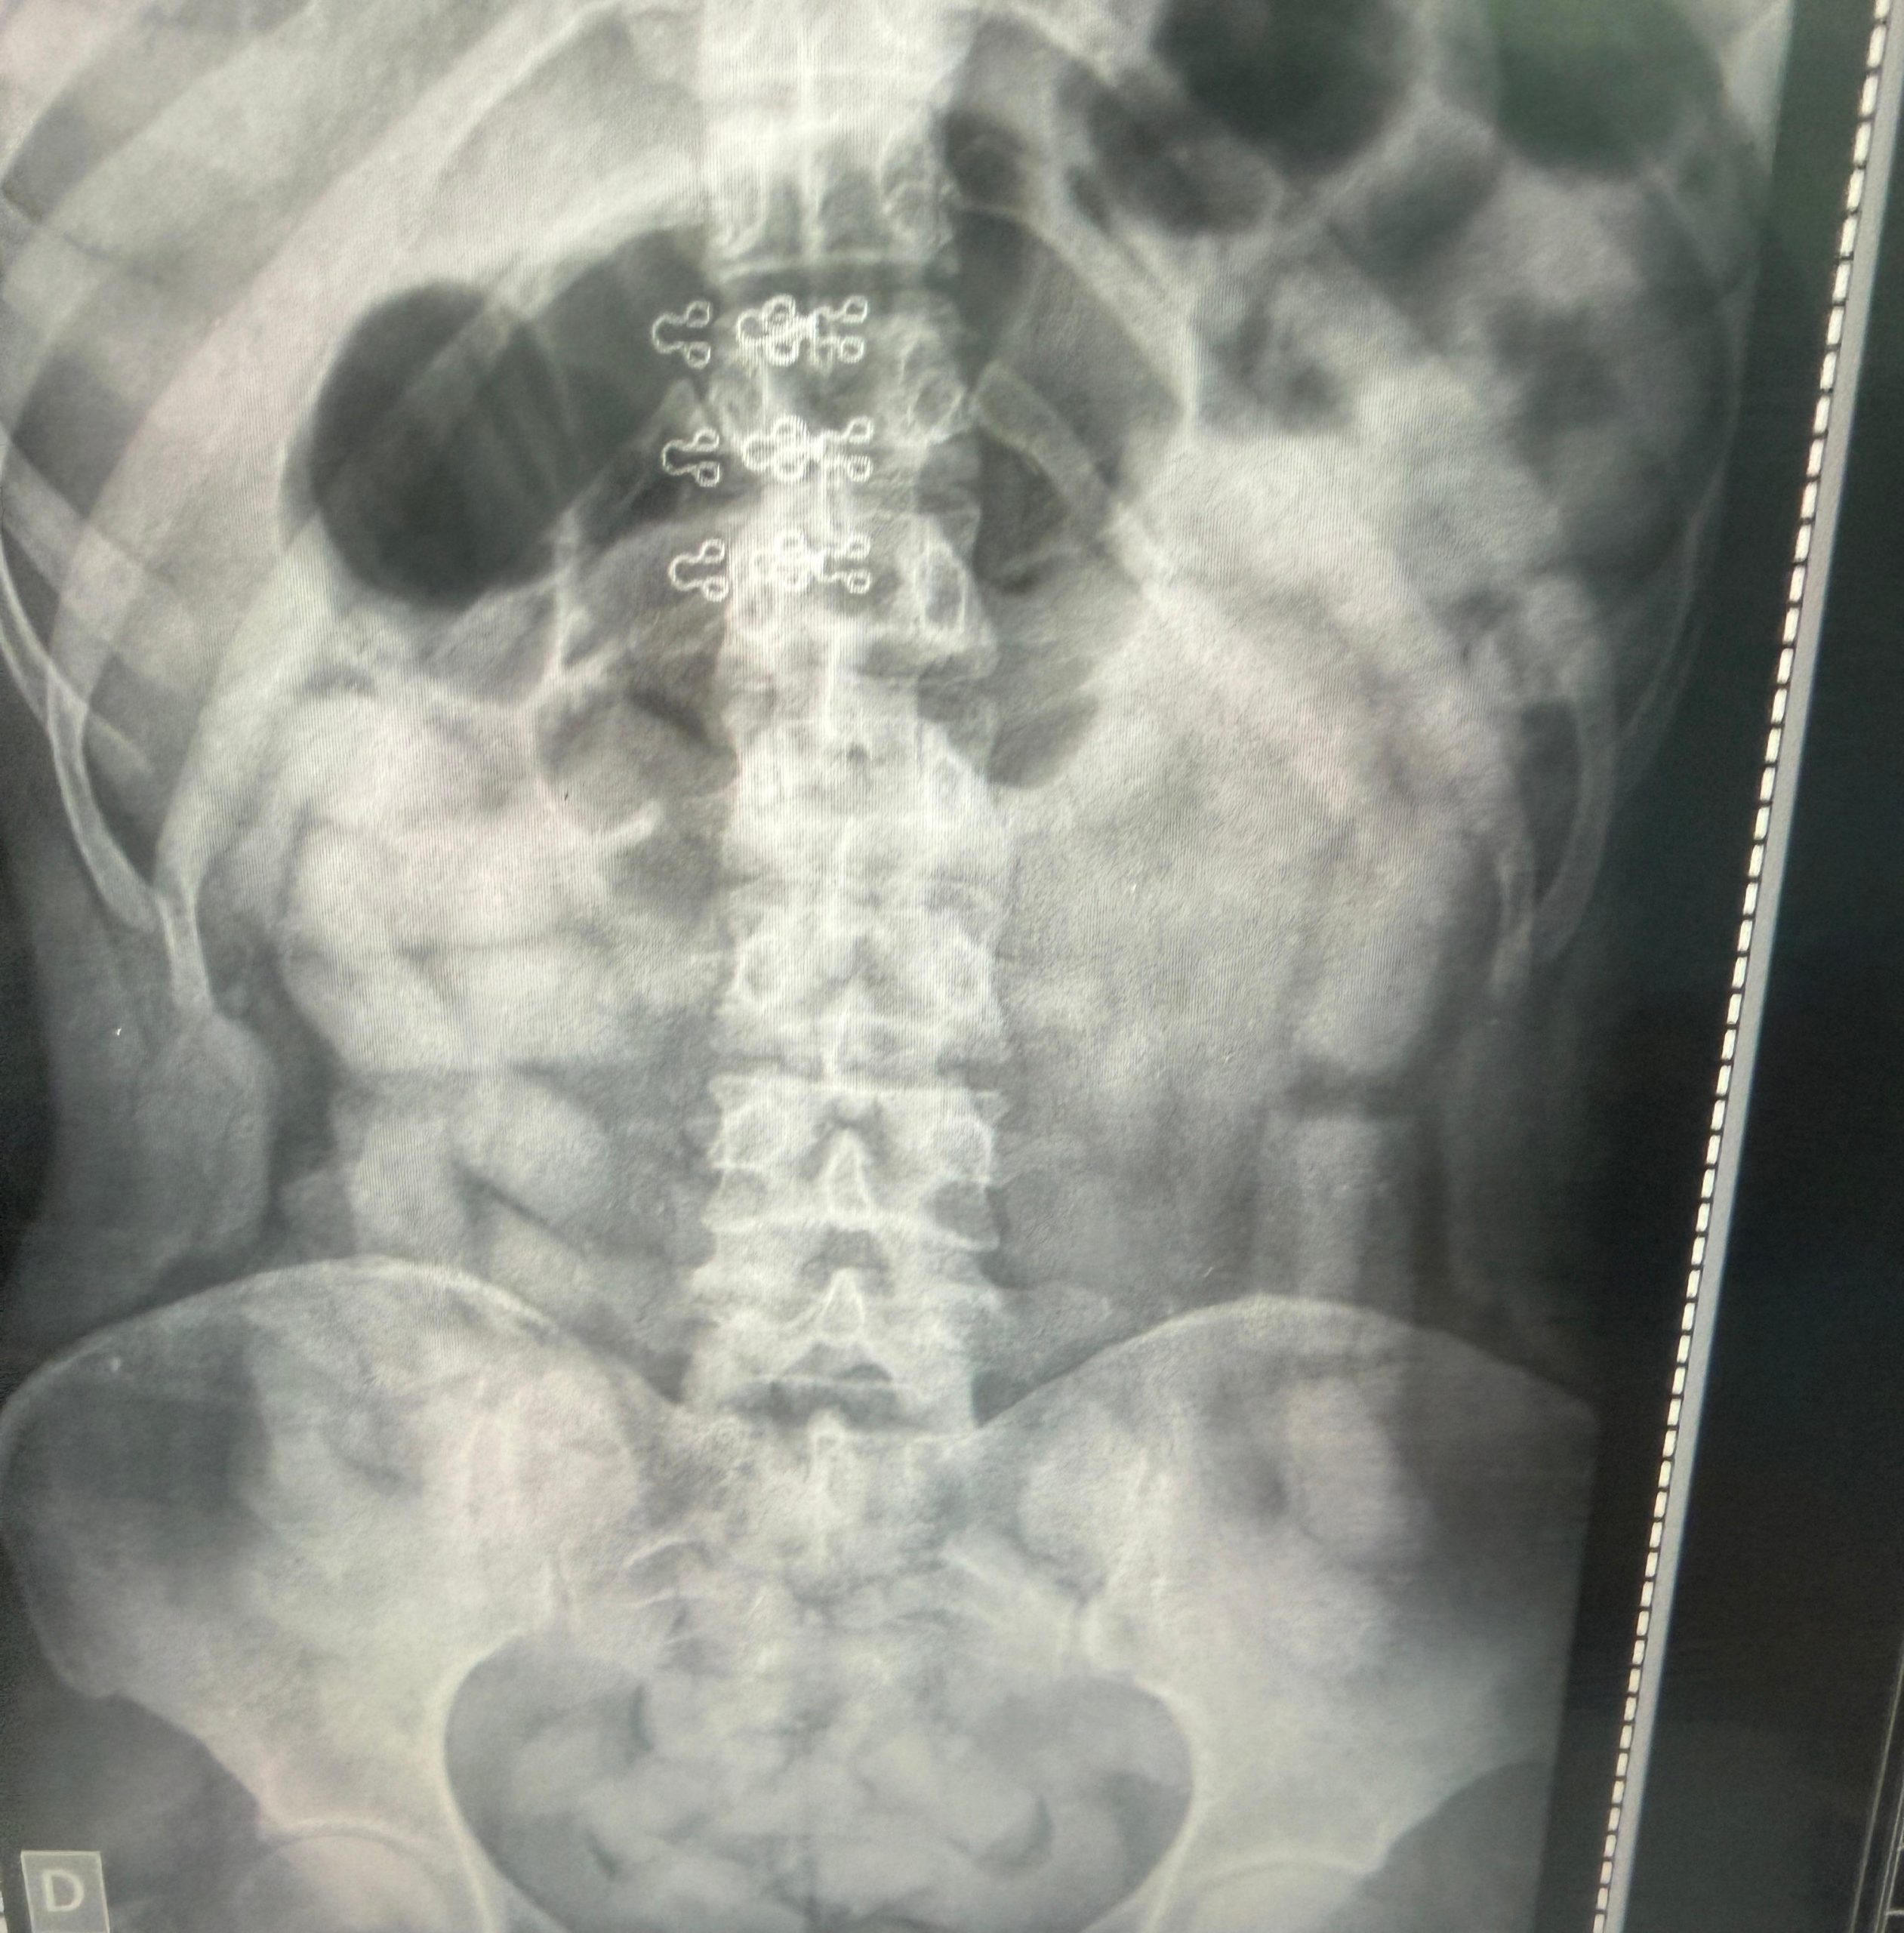

Posteriormente, y ante la sospecha de que otros pasajeros pudieran haber ingerido estupefacientes, se realizaron estudios radiográficos a la totalidad de las personas a bordo. En seis casos —cuatro mujeres y dos hombres— se detectaron cuerpos extraños en el abdomen.

Los involucrados fueron trasladados a los hospitales de Santa Ana y Los Sarmientos, donde permanecieron internados bajo custodia. Tras la expulsión de las cápsulas, se contabilizaron más de 500 dosis con un peso superior a los 6 kilos de cocaína.

En total, el personal de Criminalística y Estudios Forenses registró 752 cápsulas, que arrojaron un peso final de 10 kilos con 316 gramos del estupefaciente.